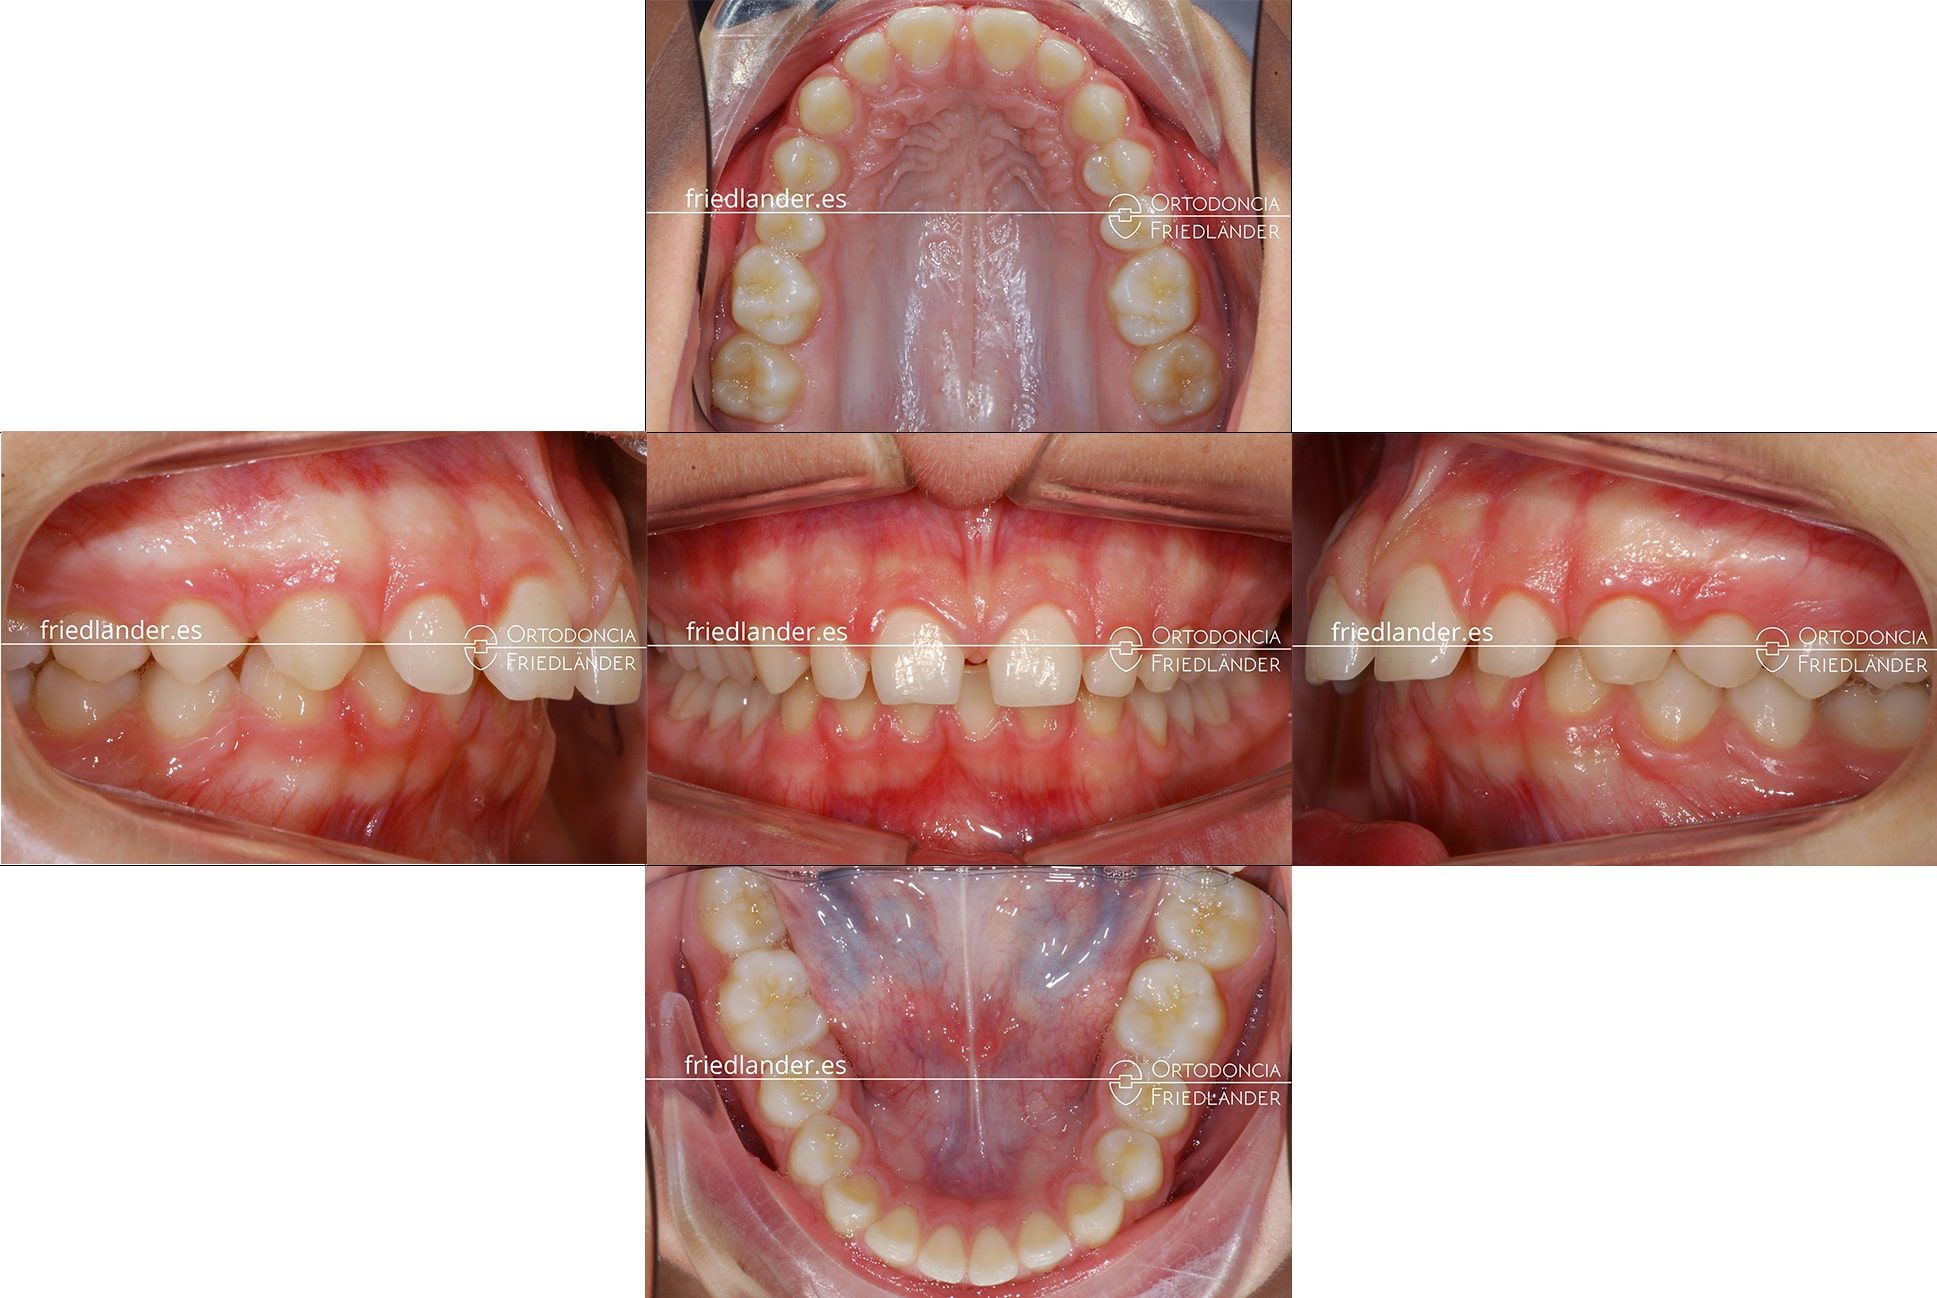

El motivo de la consulta fue que a la paciente no le gustaban los espacios entre los incisivos superiores. En la exploración clínica, de la primera visita, se observa una clase II (mandíbula retruida) con una desviación mandibular hacia la derecha de la paciente y con el resalte aumentado, diastemas (espacios) entre los incisivos superiores e inferiores y una alteración de forma de los incisivos superiores; los incisivos laterales son microdónticos (muy pequeños) y los incisivos centrales tiene forma de «tonel» son más ancho en la parte media.

Después de realizar el estudio de ortodoncia explicamos a la paciente y sus padres qué tratamiento proponemos y porqué solo arreglar los 4 dientes anteriores no era suficiente; después de comentar el estudio de ortodoncia con ellos hemos escogido el tratamiento con aparato de Herbst para avanzar y centrar la mandíbula y así corregir las clase II, continuar con ortodoncia fija de autoligado y acabar con carillas estéticas para mejorar las forma de los dientes anteriores.